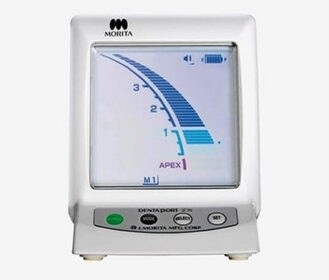

Low dose scan, high value image (Better diagnosis and treatment planning)

We provide a full range of services for both adults and children, everything from braces and clear aligners to dental implants, root canal treatment, wisdom tooth removal, whitening, and more. Whatever your smile needs, we’ve got you covered!